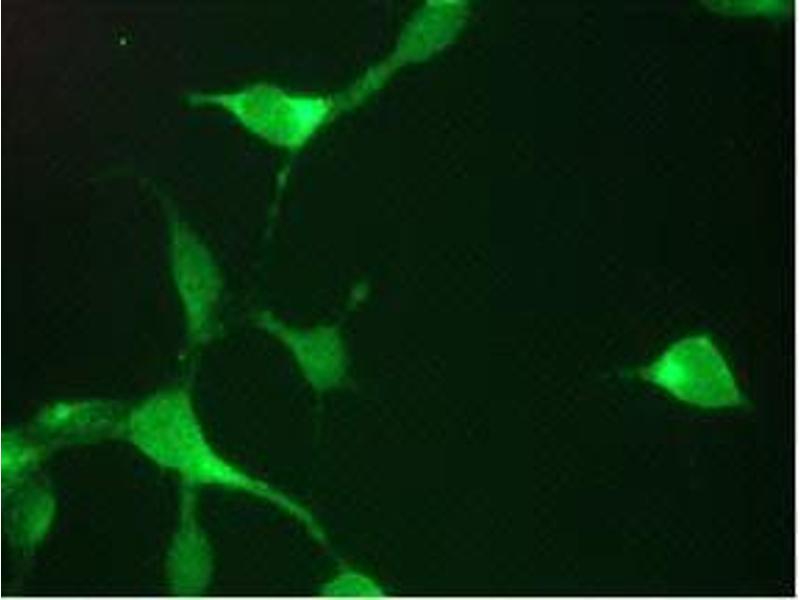

ELISA, Western Blotting (WB), Immunohistochemistry (Paraffin-embedded Sections) (IHC (p)), Flow Cytometry (FACS), Immunocytochemistry (ICC), Immunohistochemistry (Frozen Sections) (IHC (fro))

1A7 is suitable for immunocytochemistry, immuno-histochemistry on frozen and paraffin-embedded tissues, ELISA, Western blotting and flow cytometry. Optimal antibody dilution should be determined by titration.